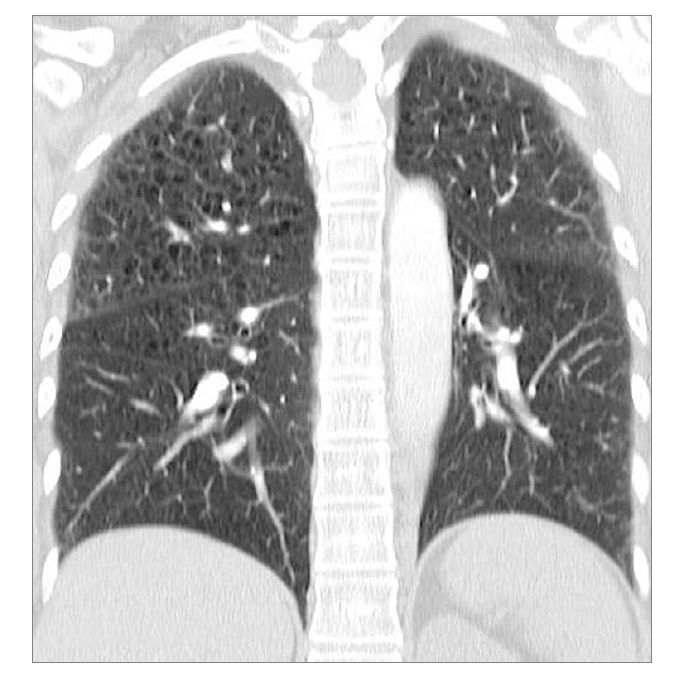

What feature is seen at the top? What condition would this be?

Blebs. Centrilobular emphysema.